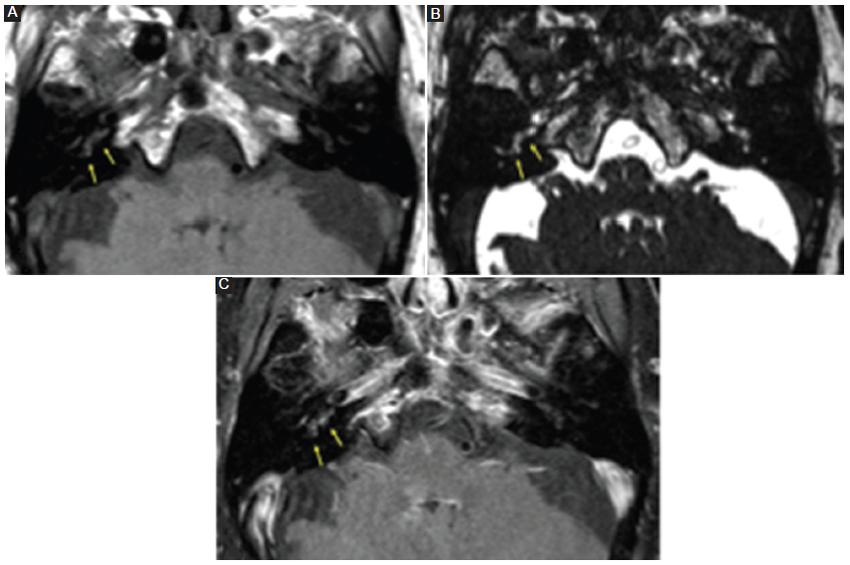

Todos los pacientes con neurinoma intralaberíntico revelaban una baja señal en la secuencia T2 AR, ligera hiperseñal en la secuencia T1 SC y realce poscontraste con márgenes bien definidos (Fig. 3). Tres pacientes con laberintitis inflamatoria (42,5%) mostraron baja señal en las secuencias T2 AR y T1 SC, y 5 pacientes (71%) manifestaban realce con el contraste (Fig. 4), con márgenes menos claros que los pacientes con neurinoma. Los 5 pacientes con laberintitis osificante presentaron baja señal en la secuencia T2 AR, y 2 pacientes (40%) tenían hiperseñal en la secuencia T1 SC (Fig. 5). Solo en 3 pacientes con laberintitis osificante se realizó secuencia con contraste, y 2 de ellos mostraron realce. Los 3 pacientes con hemorragia evidenciaron una señal alta en la secuencia sin contraste (Fig. 6) y 2 (66,7%) presentaron refuerzo poscontraste (Tabla 2).

La laberintitis es una enfermedad aguda o subaguda de causa inflamatoria o infecciosa del laberinto membranoso (espacios que contienen líquido en el oído interno). Puede manifestarse a cualquier edad, clásicamente con una hipoacusia neurosensorial súbita unilateral, a veces a lo largo de horas o pocos días, asociada a acúfenos y vértigo. Dicha clínica aguda se evidencia cuando la causa es viral; en cambio, cuando la causa es bacteriana, más habitual en la infancia, la clínica es más progresiva. El refuerzo poscontraste suele verse en la fase aguda, pero puede ser de difícil detección debido a la señal hiperintensa espontánea en la secuencia ponderada en T1, vinculada con el alto contenido proteico del tejido inflamatorio7,8.

Dada la presentación clínica similar, los hallazgos por imagen nos brindan mayor información para aproximar el diagnóstico. En la secuencia T1 CC, ambas afecciones pueden exhibir un ligero realce con el contraste intravenoso (no tan marcado como el schwannoma), y la secuencia T2 AR puede ser normal. Lo característico y lo que las diferencia es que en la laberintitis inflamatoria la secuencia T1 SC puede mostrar una señal normal o levemente aumentada, y en la hemorragia laberíntica muestra una marcada señal hiperintensa.

En nuestra muestra, acorde con estos hallazgos descritos en la literatura, solo el 42,5% de los pacientes con laberintitis inflamatoria evidenciaron señal alta en la secuencia T1 SC. En cambio, el 100% de los pacientes con hemorragia laberíntica mostraron evidente señal hiperintensa en la misma secuencia1,2.